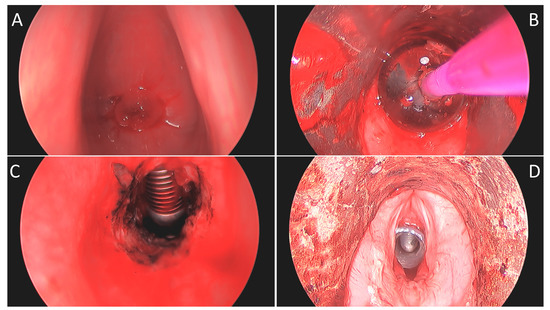

Figure 3.

Bronchoscopic images of patient “E”. (A) Initial flexible bronchoscopy showing complete fusion and occlusion of the subglottic space. (B) Intraoperative image postrecannulation of tracheal stenosis. (C) Flexible bronchoscopy at the 2-week follow-up with T-tube in place. (D) Flexible bronchoscopy after T-tube decannulation with marked improvement of tracheal stenosis.

Postoperatively, two patients (40%) were treated with antibiotics due to airway colonization. Two patients (40%) required emergency department visits for airway crusting. Of these, one patient (20%) was ultimately deemed incapable of caring for the T-tube, which was removed and replaced with a tracheostomy tube. The other required the removal of crusting on two separate occasions due to non-compliance with the cleaning regimen and capping. Four of the five patients (80%) were noted to be alive at the last chart check, with one patient being deceased for unknown reasons nineteen months after stent placement. Stent decannulation was attempted in three patients (60%); it was successful in one (Figure 3) and failed in the other two patients.